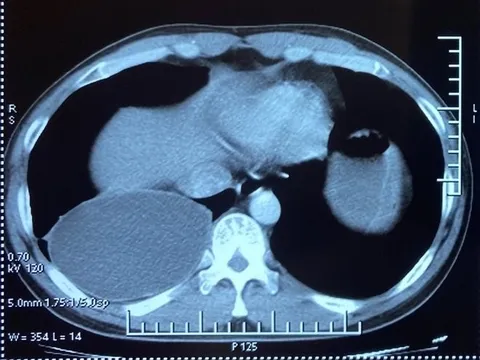

Khám, tầm soát phổi miễn phí cho người dân tỉnh Thừa Thiên-Huế

Chỉ trong sáng nay (18/1), hơn 600 người dân trên địa bàn tỉnh Thừa Thiên-Huế đã được khám, sàng lọc miễn phí bệnh ung thư phổi và các bệnh lý về phổi.